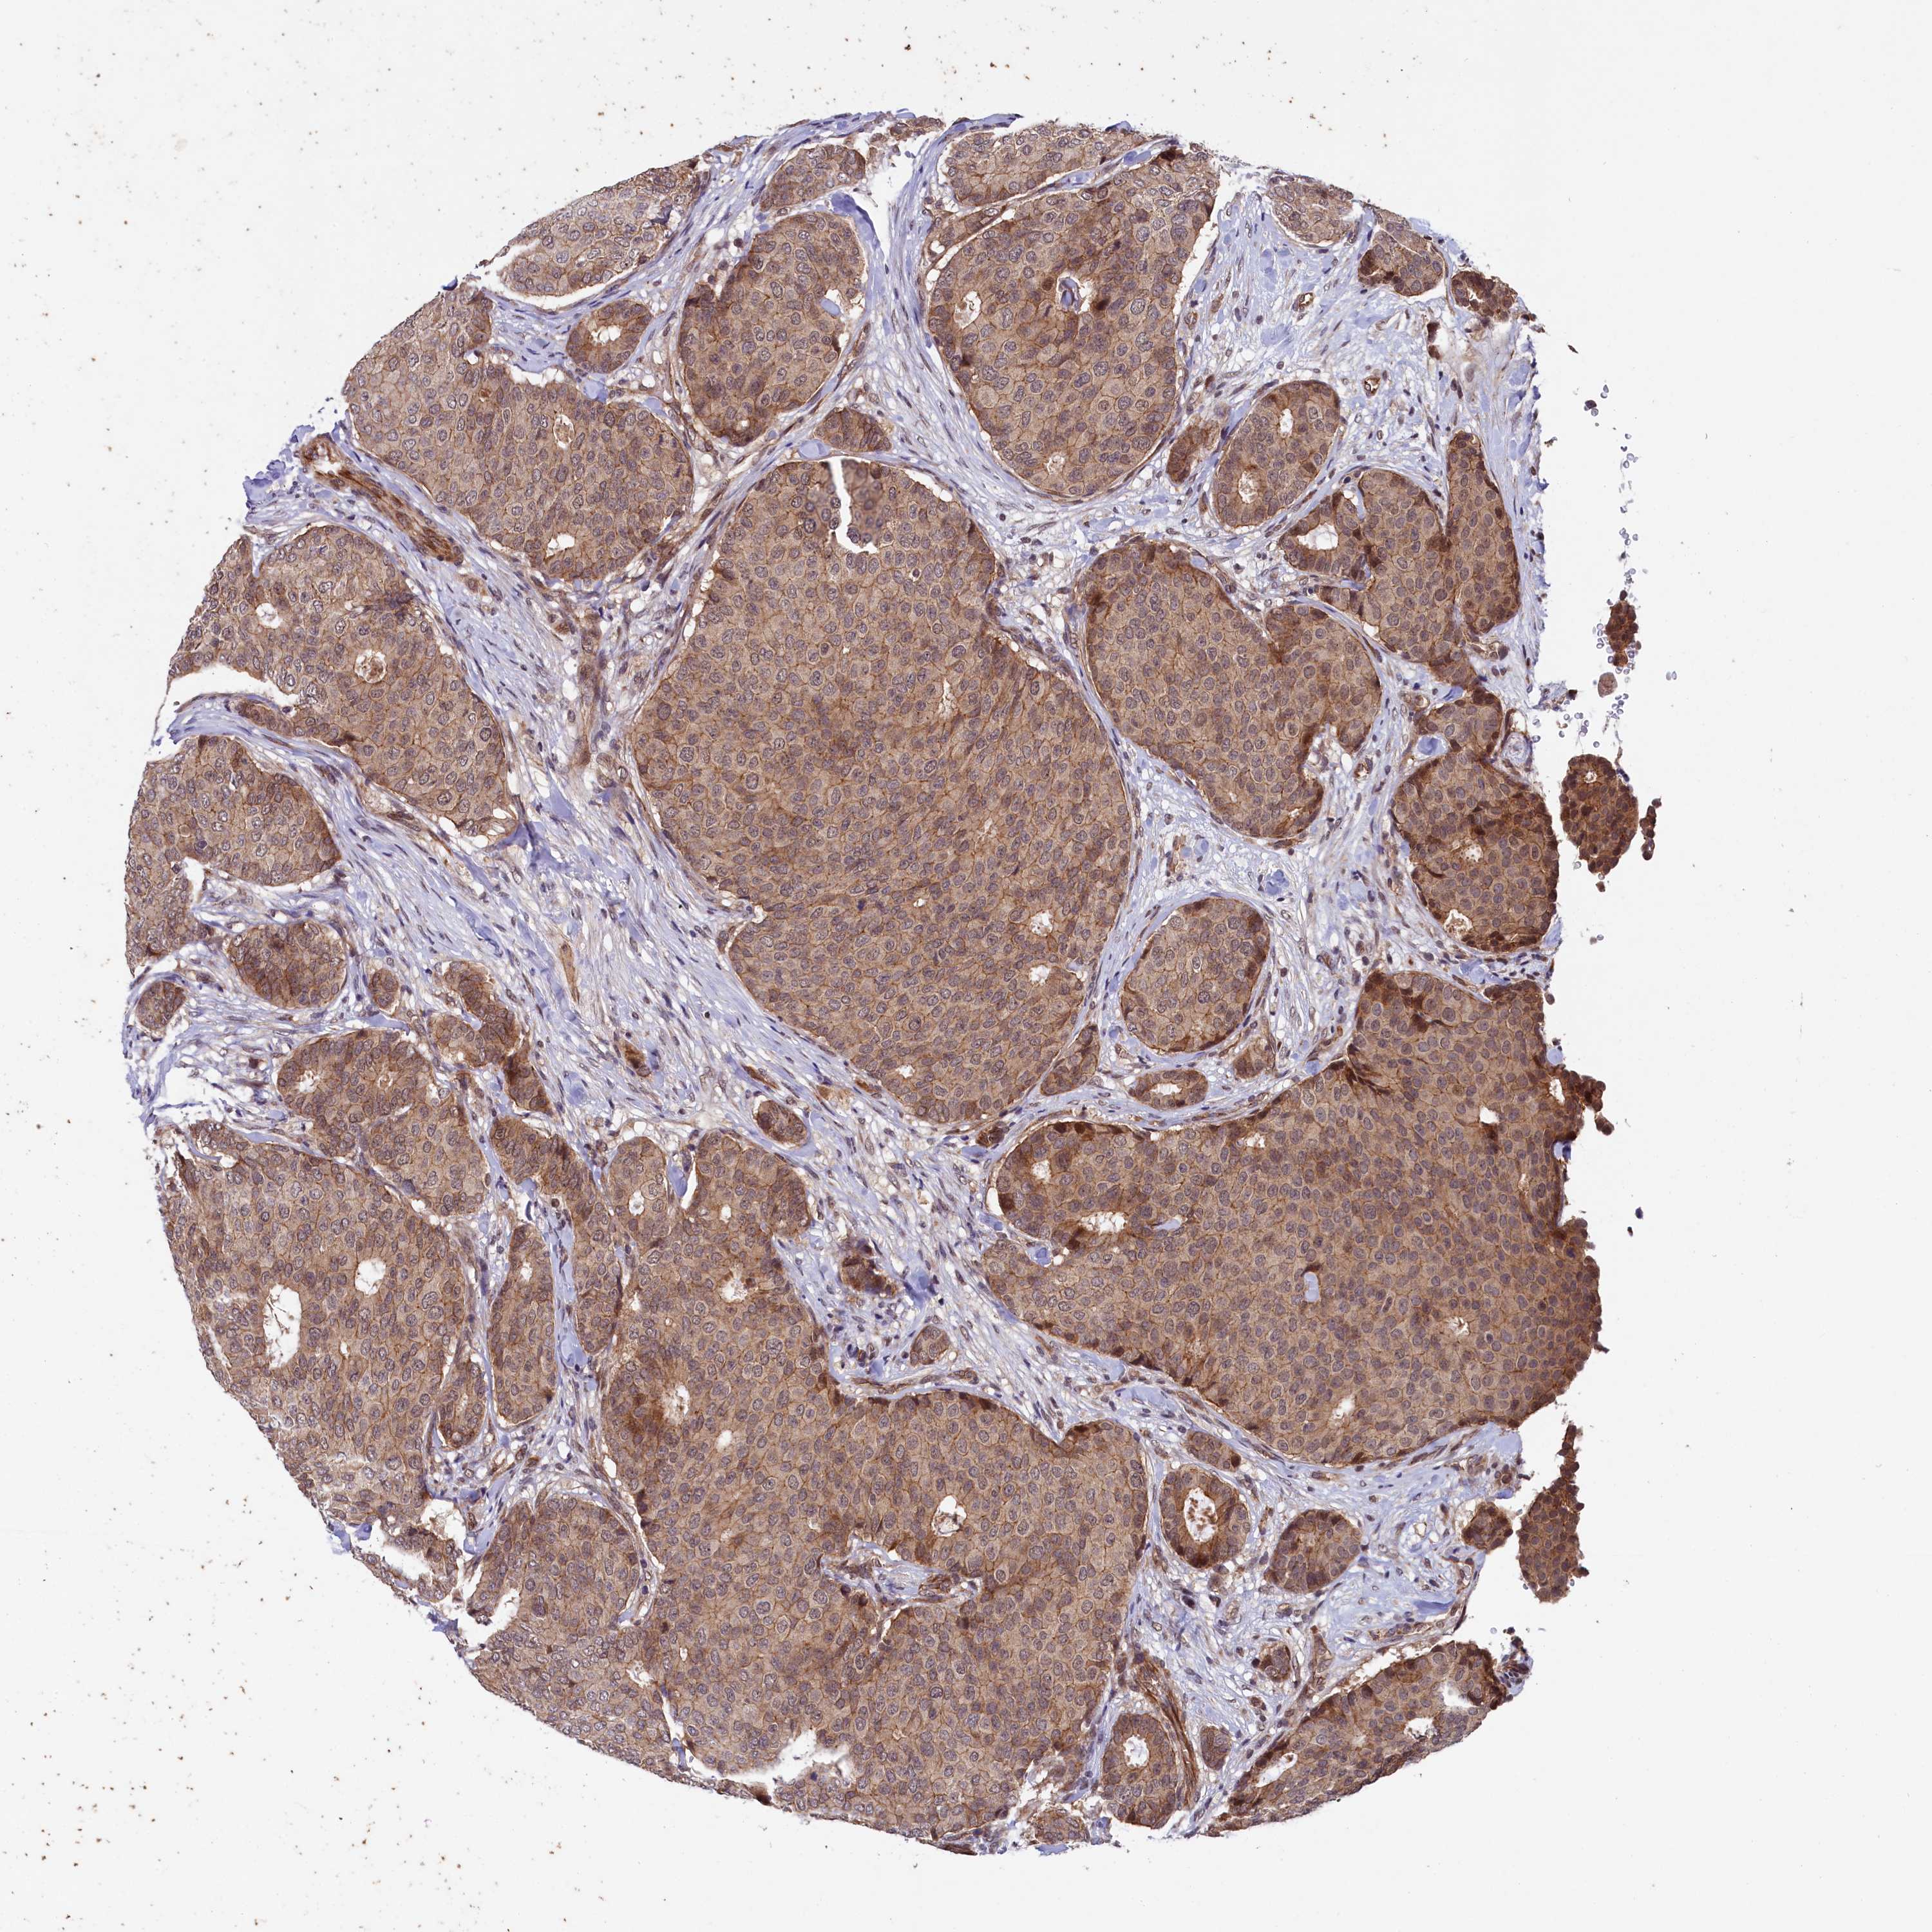

CANCER BREAST CANCER Show tissue menu

BRCA TCGA BRCA VALIDATION PROTEIN EXPRESSION